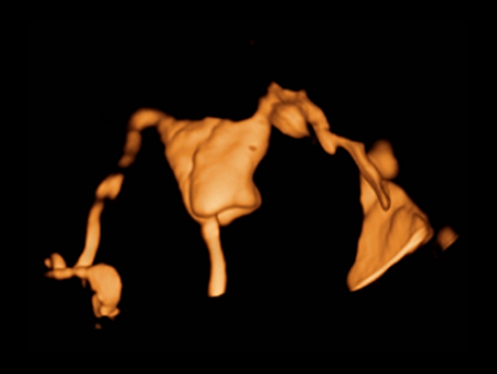

DC-80A con X-Insight mette a disposizione strumenti di una intelligenza eccezionale specifici per la cura della donna, dalla fertilit├Ā allo screening prenatale, e al post partum.

Immagini cliniche